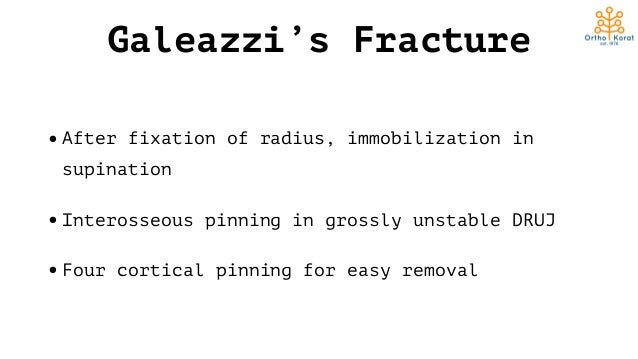

The pain started 72 days back when the patient sustained a road traffic accident and fell from his motorbike on an outstretched hand, since then, he noticed the deformity in his forearm, and he first thought it was a simple contusion or bruise. Galeazzi fracture-dislocations are usually managed acutely due to the apparent deformity, pain, and disability suffered by the patient, we have searched the literature and only found one case reporting a chronic Galeazzi fracture-dislocation, and therefore, we present our experience with this rare injury.Ī 27-year-old man of Eastern Asian descent presented to our outpatient clinic with a complaint of the right forearm pain and deformity for over 2 months. In pediatrics, however, Galeazzi fracture can be amenable to closed treatment with satisfactory outcomes due to several reasons including thick periosteum, stronger ligamentous restraints, and higher bone modeling capacity. Historically Galeazzi fractures is adult were treated with open reduction and internal fixation of the radius fracture with or without DRUJ repair and pinning, the is largely due to the highly unsatisfactory outcomes following closed treatment and chronic disability. On the other hand, two classification systems classify the fracture based on its distance from the DRUJ, the most commonly used is the one by Retting, in which the fracture is either more than 7.5 cm away from the DRUJ or less, the main rationale behind this classification is that fractures < 7.5 cm are more prone to DRUJ instability according to the results of this study. Several classification systems have been proposed for Galeazzi fracture-dislocation, the first was described by Walsh, in which the fracture was classified based on its angulation, the position of the forearm (supination of pronation) on axial loading of the fractures will contribute to its apex (apex volar or apex palmar). The IOM also has a complex structure of bands and cords that prevent translation of the radius and ulna and also transmit axial and rotational forces, the central band is the main restraint and stabilizer within the IOM. Galeazzi fractures are inherently unstable due to the disruption of the DRUJ and possible disruption of the interosseous membrane (IOM), the triangular fibrocartilage complex (TFCC) is the main stabilizer of the DRUJ and the dorsal and volar radioulnar ligaments are the most important ligaments within the TFCC.